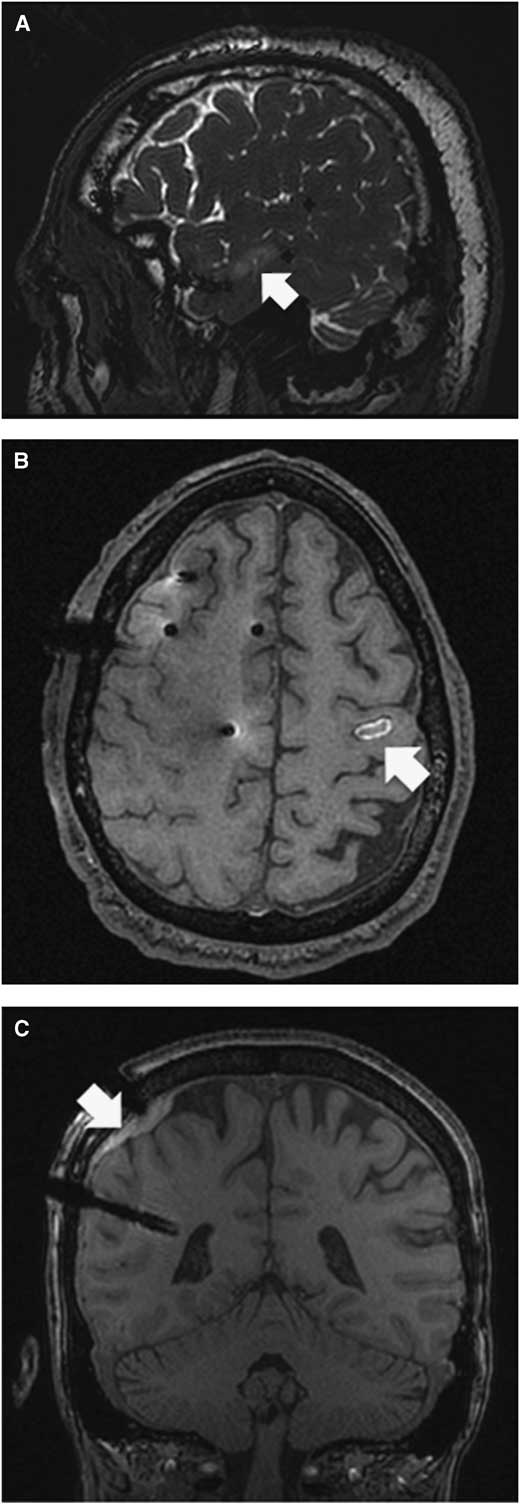

A careful review of each patient’s MRI with the electrodes in situ revealed four unexpected findings (three in the manual group and one in the robot-assisted group, p=0.287). Figure 2A demonstrates an area of contusion without hemorrhage that resulted from a penetration of the anchoring screw through bone that had been weakened by previous pin fixation with the manual technique. Figure 2B shows a hemorrhagic contusion that likely occurred from an unintended perforation of the dura and cortex at the time of craniostomy with the manual technique. Figure 2C shows a subdural hematoma that likely occurred from an unintended perforation of the dura and/or laceration of a cortical vessel at the time of craniostomy with the manual technique. Figures 3A and 3B show venous congestion in the left posterior temporal area, most likely secondary to venous compression or coagulation with the robot-assisted technique. Figures 3C and 3D demonstrate its resolution at 3 months post-explantation.

Figure 2 (A) Patient 12. T2 sagittal section showing a non-hemorrhagic contusion (white arrow) on the second temporal gyrus. The bone had been weakened by prior pin fixation where the anchoring screw penetrated the cortex. A small skin incision was required to retrieve the anchoring screw. (B) Patient 17. T1 axial section showing a hemorrhagic contusion most likely due to penetration of the cortex with the drill bit. This was not caused by insertion of the stylet or electrode since it was the intended site of an epidural contact. (C) Patient 6. T1 coronal section showing a subdural hematoma most likely due to unintended penetration of the dura and/or laceration of the cortical vessel.